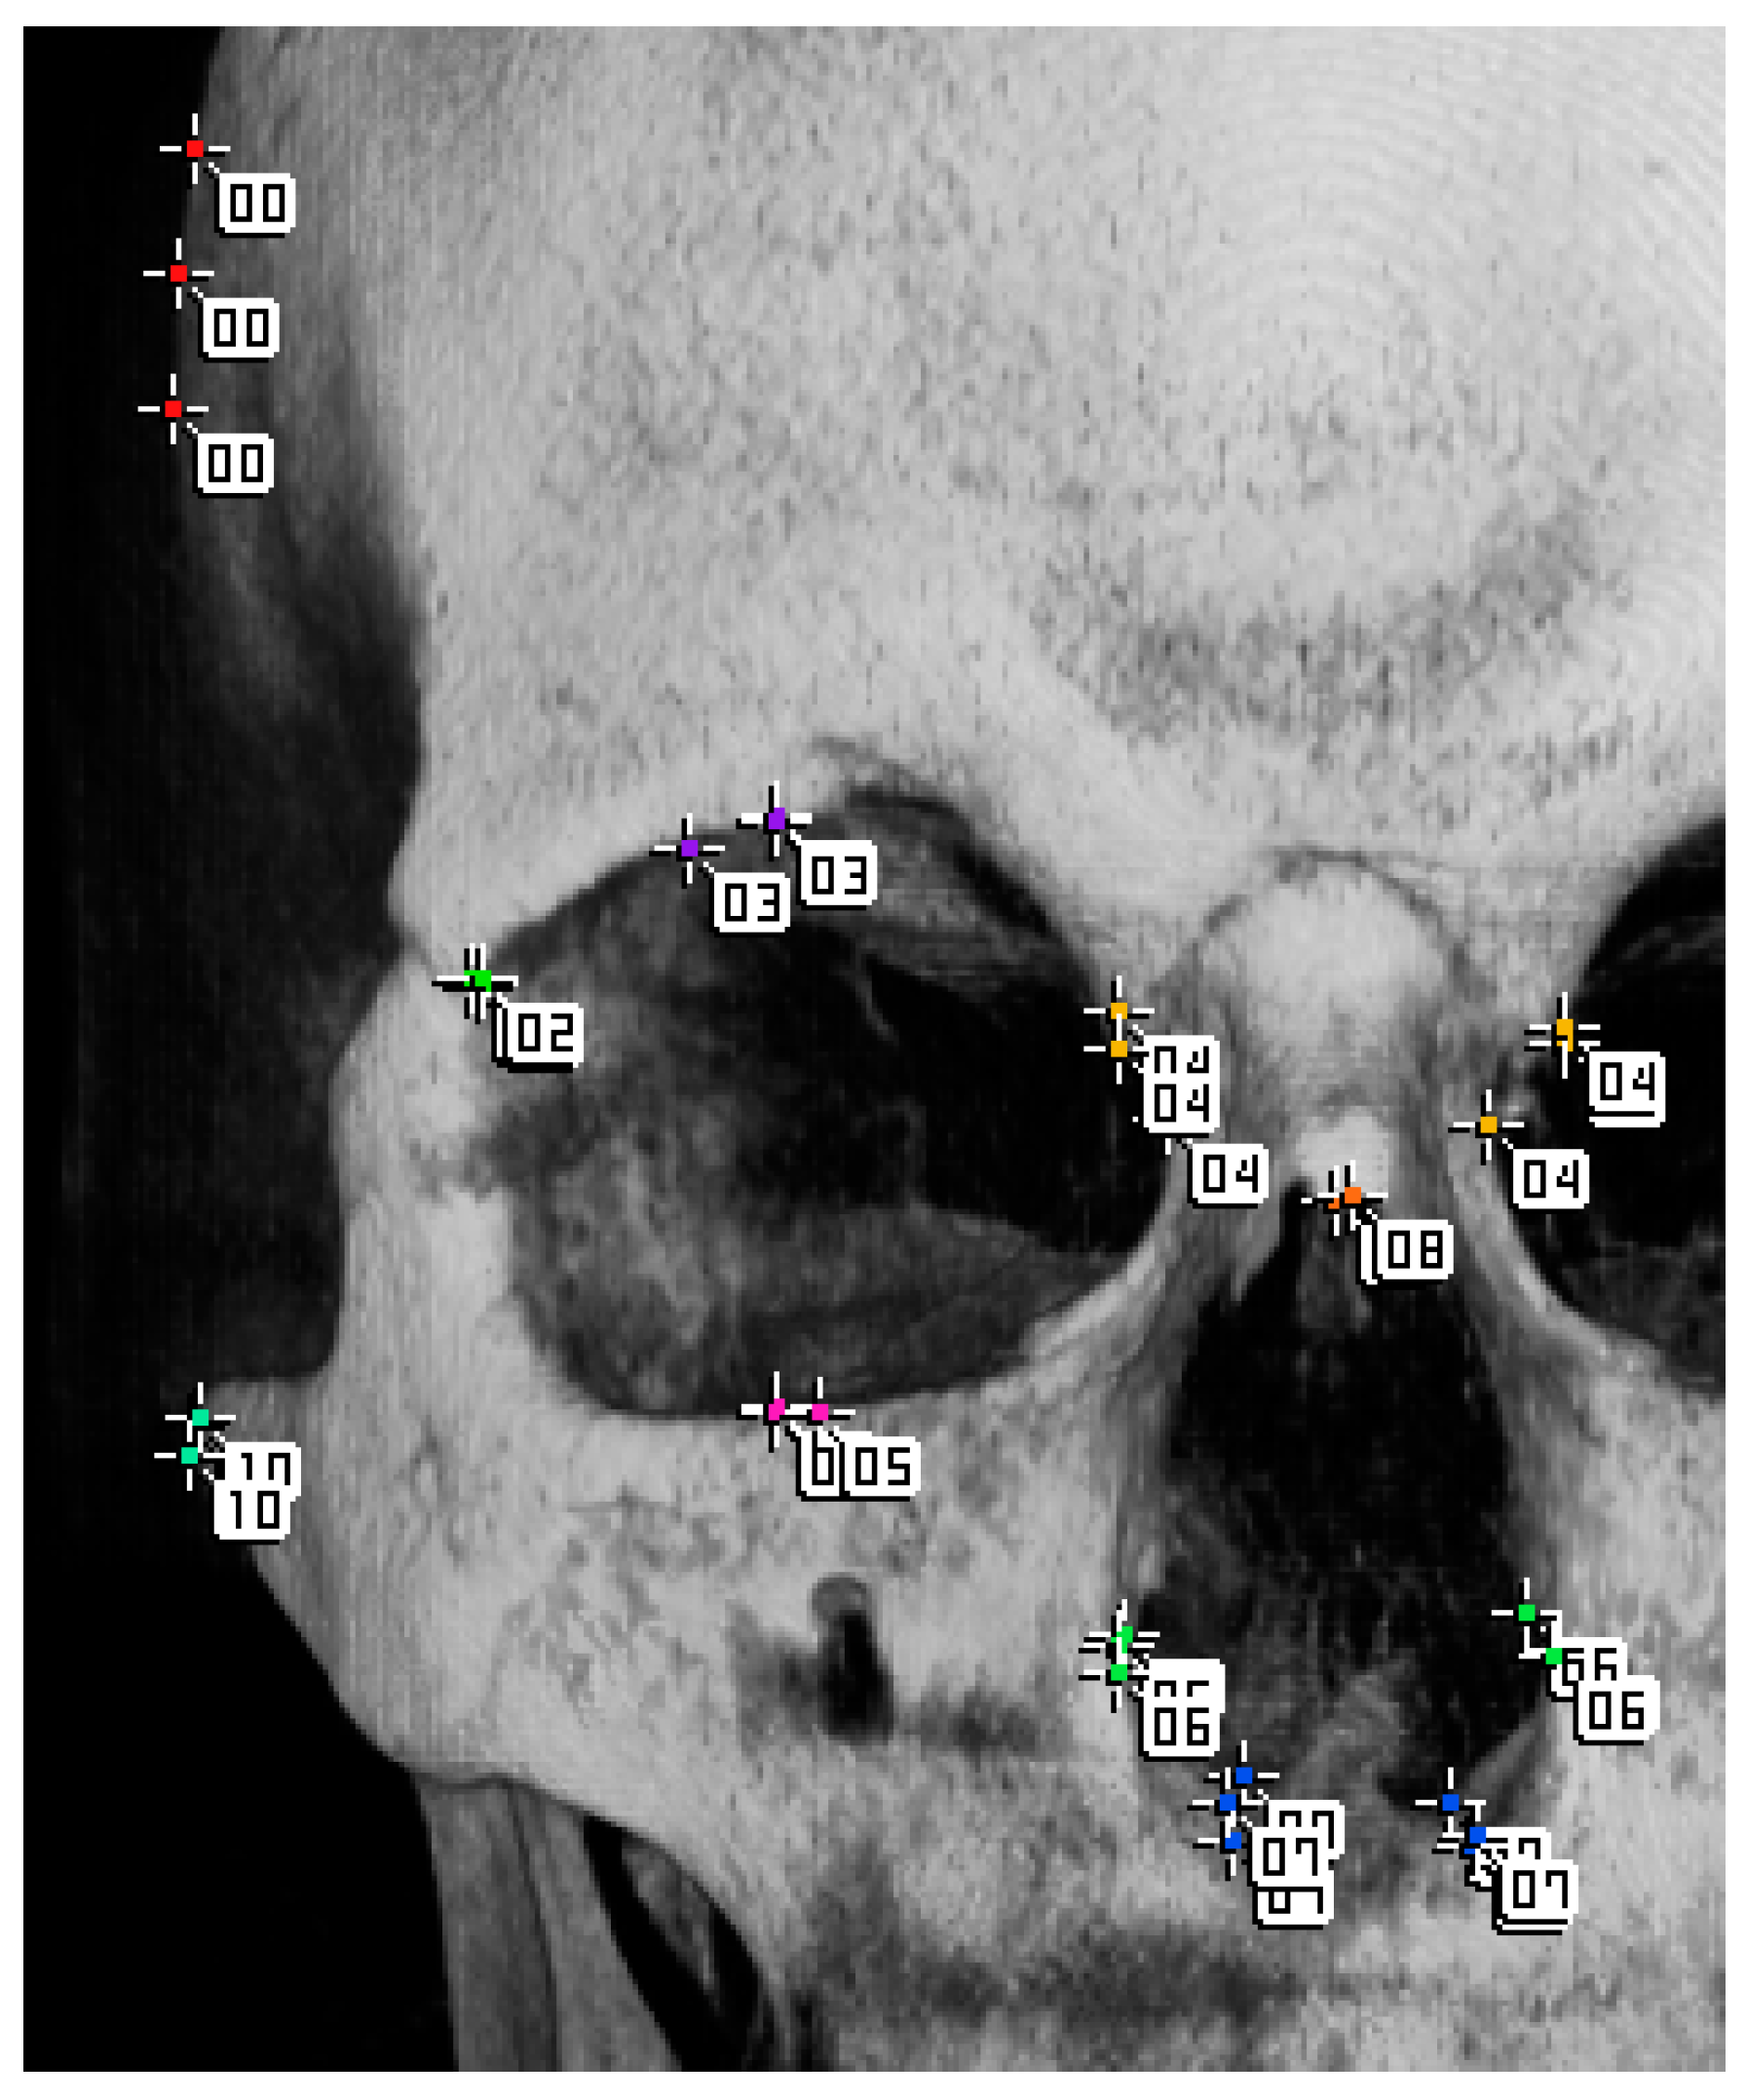

We distributed several examples of the same data to three orthodontists and asked them to arrange the markers; then, we overlapped their arrangements and checked the variations in position (Figure 8).

Figure 8. Measurement markers individually placed by three orthodontists for the same patient are superimposed on one image. Three markers with the same number are placed, and each position is misaligned. There is little deviation in the placement of marker 02. In contrast, marker 00 is placed differently by each orthodontist.